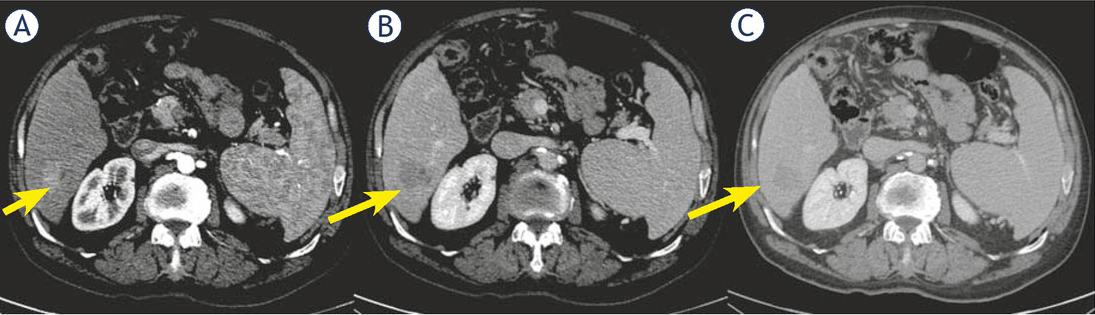

Only two cHCC-CCA patients (18.2% of cHCC-CCA) showed capsule appearance while 9 cHCC-CCAs (81.8% of cHCC-CCA) did not have this feature (Figure 2).

Woman 68 y with combined hepatocellular-cholangiocarcinoma (cHCC-CCA) on VI hepatic segment. Multidetector computed tomography (MDCT) study. The nodule shows hypervascular appearance (arrow) during arterial phase of contrast study (A), with wash-out appearance (arrow) and without capsule appearance (arrow) during portal and late phase of contrast study (B and C).

Thirty-one (60.8%) true HCC showed capsule appearance and 19 (37.2%) true HCC did not show this feature.